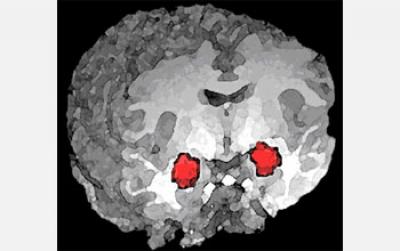

A research team led by Karl Deisseroth, associate professor of psychiatry and behavioral sciences and bioengineering, identified two key pathways in the brain: one which promotes anxiety, and one which alleviates anxiety.

The pathways are in a brain region called the amygdala. Prior research suggests the amygdala plays a role in anxiety, but earlier studies used widespread modifications of the amygdala, through drugs or physical disruption of the brain region, to study the way in which it affects anxiety. This new work, published in this week's Nature, uses a tool called optogenetics--developed by Deisseroth and recently named Method of the Year by Nature Methods --to specifically tease out which pathways contribute to anxiety.

Using optogenetic manipulation of various amygdala pathways, Deisseroth and colleagues examined how mouse behavior was affected. Since mice display anxiety-related behaviors in open spaces, they measured changes in anxiety by analyzing how much time mice spent exploring the center of an open field, or exploring the length of a platform without walls.